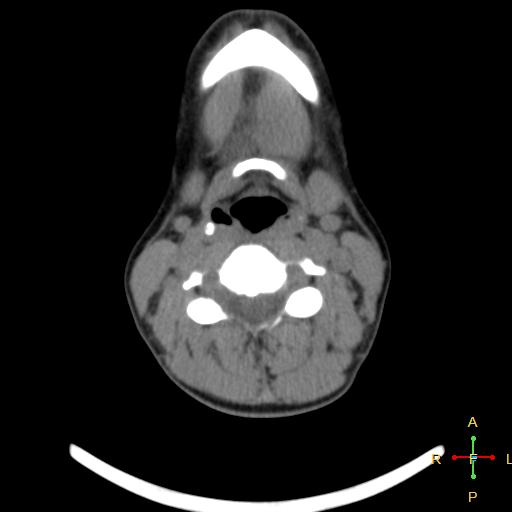

Добрый вечер! Помогите, пожалуйста,разобраться в МСКТ. Женщина, 55 лет. 27 января 2014г прооперировали по поводу ПРЩЖ с mts в лимфоузлы шеи , тиреоидэктомия с центральной лимфодиссекцией и футлярно-...

здравствуйте,уважаемые доктора!папе в апреле 2012 году поставили д-з рак носоглотки Т4N1М0.( гистология- недифференцированный рак) было выполнено комбинированное лечение ( 3 курса ПХТ, лучевая...